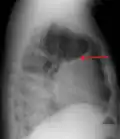

A pleural effusion as seen on lateral upright chest x-ray

Pleural effusion as seen behind the heart.[20]